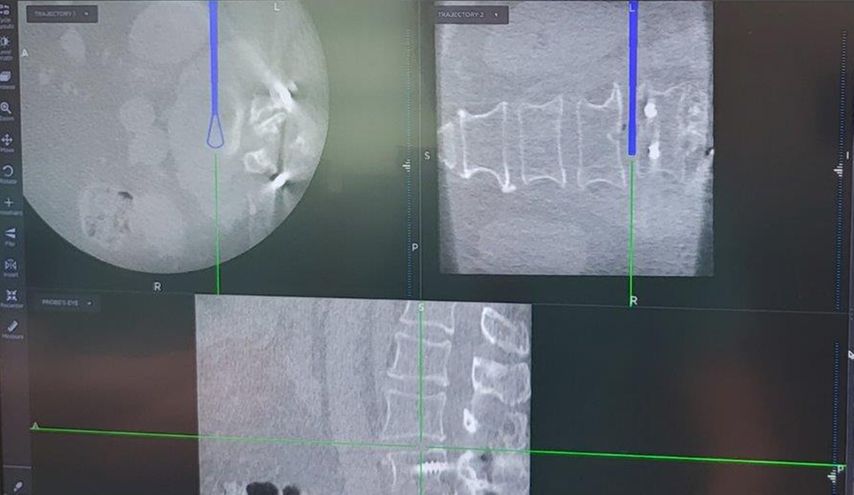

TLIF über Mittellinienzugang mit Schrauben in „cortical bone trajectory“. Bei der 63-jährigen Patientin bestand eine degenerative Spondylolisthese Meyerding Grad I mit Facettengelenkszysten und Wirbelkanalstenose (Abb. 8). Klinisch bestanden Lumboischialgien mit Ausstrahlung dem Dermatom L5 bds. entsprechend. Es wurde ein Mittellinienzugang durchgeführt und zuerst wurden navigierte Schrauben in „cortical bone trajectory“ platziert (Abb. 9). Anschließend erfolgten eine Facettektomie L4/5 links und eine Dekompression des Wirbelkanals. Abbildung 10 zeigt, dass der Hautschnitt aufgrund der mittelliniennahen Schraubenköpfe klein gehalten werden kann. Klinisch wurden die lumbalen Schmerzen wie ausstrahlende Beschwerden 1 Jahr postoperativ annähernd vollständig behoben, die korrespondierende Röntgenkontrolle ist in Abbildung 11 dargestellt.